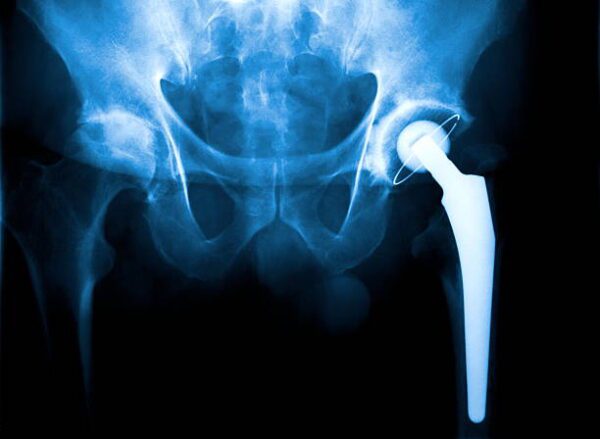

Klubo sąnario operacija yra reikalinga procedūra, kuria siekiama pagerinti paciento gyvenimo kokybę ir sumažinti skausmą dėl klubo sąnario problemų. Tačiau, kaip ir bet kuri chirurginė intervencija, ji gali sukelti tam tikras komplikacijas ir reikalauti atsakingo pooperacinio laikotarpio. Ši eseje nagrinėsime svarbiausius klausimus, susijusius su klubo sąnario operacijomis. Visumoj, klubo sąnario operacija gali atnešti daug naudos, … Tęskite Klubo Sanario Operacijos: Iššūkiai ir Nauda skaitymą